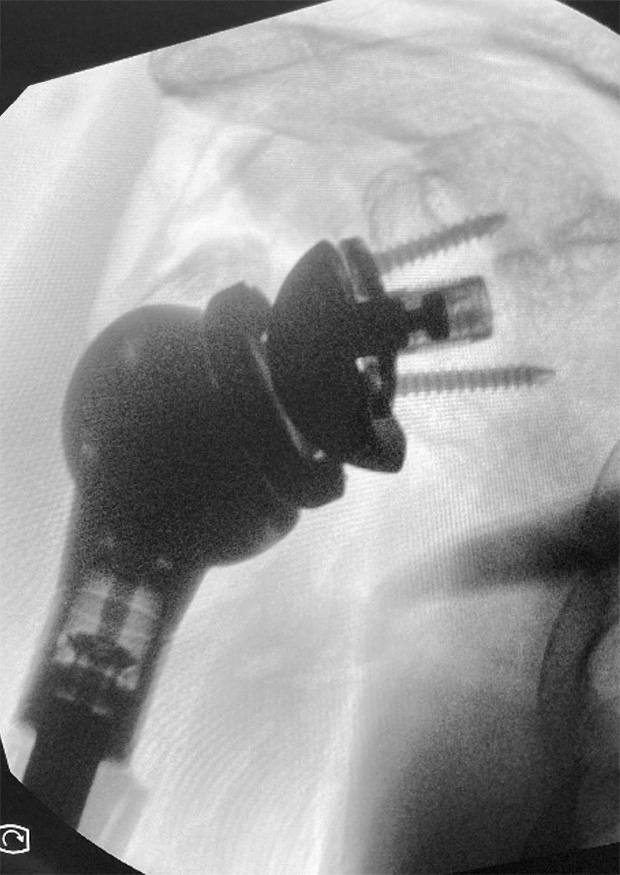

Post-op

- Pictures 12 and 13: post op x-rays with MEGA C Upper Limb and LINK Embrace components

- Good caudal overhang of eccentrical glenosphere and voluminous Proximal Body for appropriate deltoid pre-tensioning

- Distal Stem, cemented and well fixed